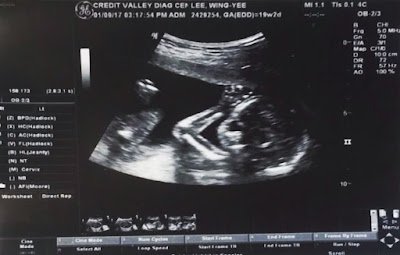

Hello World! Renee and I are pleased to introduce to you our newest addition in the making! We and the kids are super excited and can't wait to meet little A5! She is due January 24th, 2018. We just went for the 20-week ultrasound yesterday and yes, it will be our 4th girl! Athan was a little disappointed that he wasnt going to have a littel brother, but Audrey was very pleased! Lol!